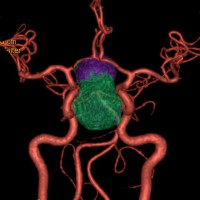

- 内頚動脈や他の頭蓋内動脈の損傷:これはあってはならないことですが,もっとも重症の合併症です。手術中に脳の動脈(内頚動脈や前大脳動脈)を破ってしまうことです。くも膜下出血になって,時には死亡することもあります。2010年以降の内視鏡手術で,0.3 – 1%くらいの頻度と報告されています。

左は下垂体腺腫(緑の腫瘍)が内頚動脈に挟まれていることを示しています。

中央は手術前の下垂体腺腫で,視神経も正常下垂体も位置はわかりません。

右は手術翌日の画像です。黄色の矢印の先が残した正常下垂体組織です。桃色の矢印の先に視神経(視交叉)がはっきり見えています。術後の一時的な尿崩症がありました。クモ膜が残っているので髄液漏は生じませんでした。でも正常下垂体組織(黄色矢印)も視交叉も腫瘍に圧迫されてペラペラになっていますから,いつもうまく行くとは限りません。